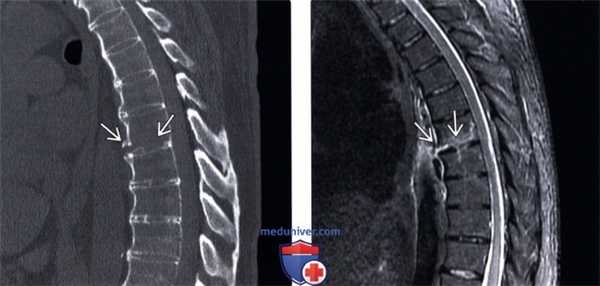

(Слева) КТ, сагиттальный срез (костный режим): перелом, линия которого проходит в области нижней части тела позвонка параллельно замыкательной пластинке. Передний отдел зоны перелома расширен, что свидетельствует о гиперэкстензионном повреждении.

(Справа) На сагиттальном STIR МР-И отмечается патологические усиление сигнала в области передней продольной связки и нижней части тела позвонка. В области задней продольной связки и задних элементов достоверных признаков изменения сигнала не видно.